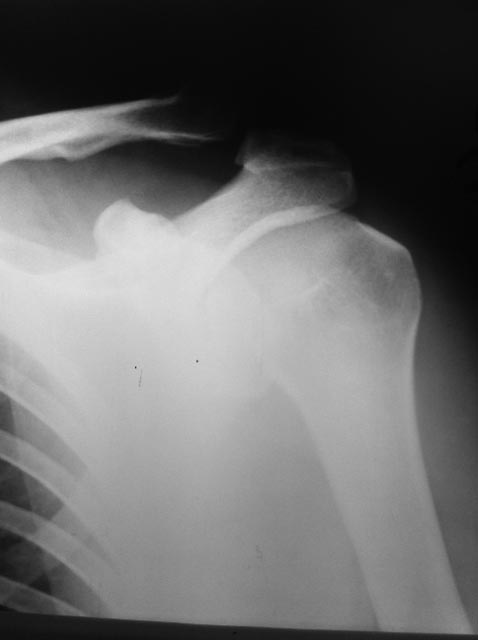

Дайте добрый совет коллеги плиз - вывих акромиального конца ключицы

Травма в результате падения на лыжах 4.01.2013Мнения коллег разошлись.Стоит оперироваться или можно обойтись консервативно?

На Вашей рентгенограмме повреждение все же следует трактовать как подвывих.

Обычный критерий таков: если ключица сместилась более чем на половину толщины, то показано оперативное лечение, если меньше - консервативное. В Вашем случае "не то, не сё". Выполните рентгенографию с нагрузкой пострадавшей руки (5-7 кг). Причем лучше привязать к запястью, а не давать груз в руки. Не будут напрягаться мышцы и "картинка" будет более достоверной. Не помешает рентгенограмма и здорового сочленения. Если увидите, что смещение увеличилось, то вопросов нет. Если не изменилась, то подходы могут быть разные. Что следует учитывать? Возраст, профессию, активность человека. Если оставить ключицу в таком положении, то это будет «уже не та рука». Где тонко, там и рвется. В следующий раз уже более слабое воздействие вызовет вывих и он, наверняка, будет более серьезным. При физических нагрузках со временем могут появляться боли (это же все-таки сустав и явления артроза в нем, несомненно, разовьются).

Так что, если эта рентгенограмма касается нестарого, активного человека, то мое мнение - показана операция. Методов много и разбирать их здесь вряд ли уместно. Но критерии выбора метода операции должны быть следующими: наименьшая травматичность, желательно меньше «железа», хорошее владение этим методом оперирующим хирургом.